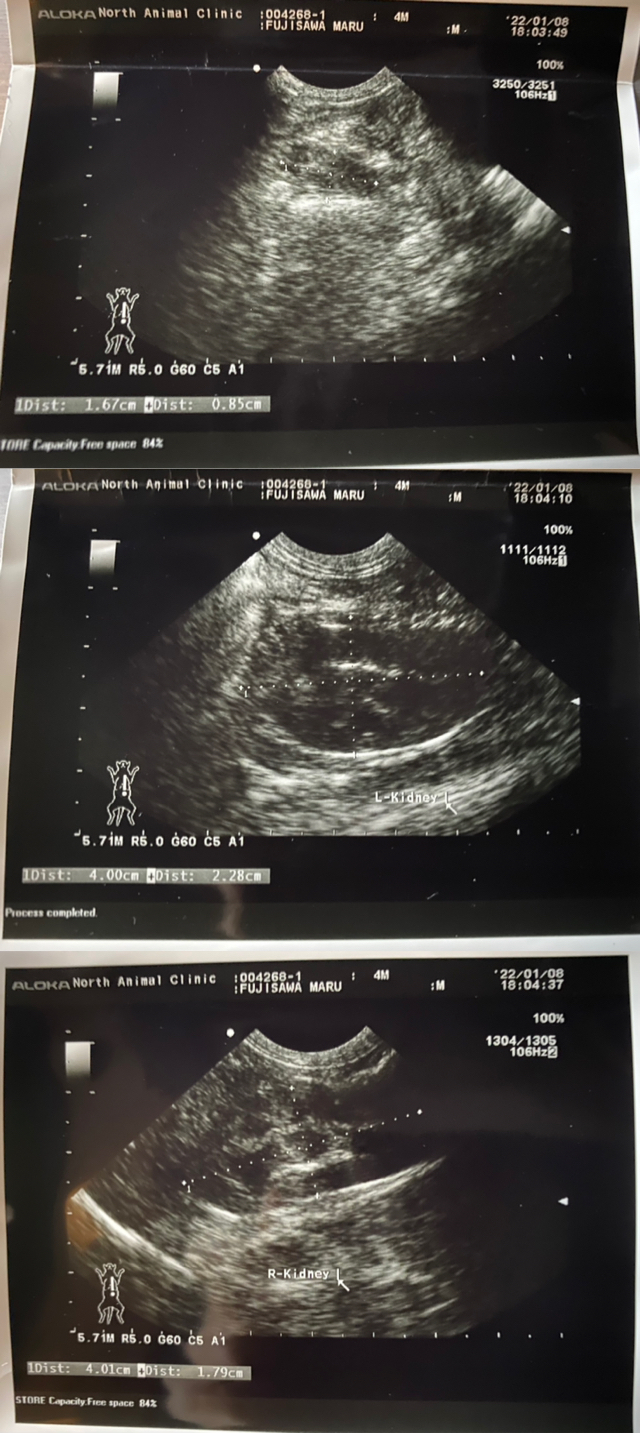

不安になり、12月29日に他動物病院へ連れて行ったところ、胸水が溜まっていて呼吸がとても困難な状態だと伝えられました。

更に色々と検査をしていただき胸水も抜いてもらうことになりましたが、小さな身体ですし痛くて暴れてしまうのもあり、全ては抜けませんでした。

FIPは「ウェットタイプ」と「ドライタイプ」、もしくは「混合タイプ」に分類されます。 円(マル)の場合は、貧血.微熱.肉芽腫.胸水があるので、混合タイプのFIPだと診断されています。

以下に病院にて診察・検査・治療薬処方の際に出ている明細書を載せさせていただきます。

(現在:治療.投薬中)

投薬初期(22.01.08~22.02.04)で

3,300円(100mg)+6,600円(200mg)=9,900円